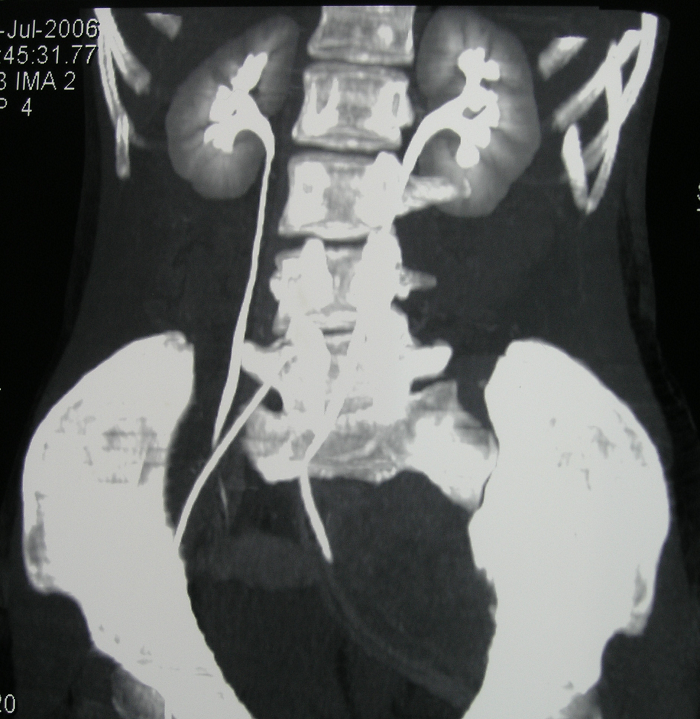

6、病例6:女 18岁 左半骨盆骨肉瘤,全身及肿瘤局部选择性动脉灌注大剂量化疗后行肿瘤切除人工半骨盆假体置换术

图 34、35、36 术前CT:肿瘤体积巨大,压迫

输尿管、膀胱等盆腔脏器